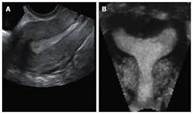

ניתן להתרשם מקיומם של ממצאים חריגים באברי הרביה, כגון גושים, ציסטות באגן, שרירנים או פוליפים בחלל הרחם. במצבים מיוחדים משתמשים בנוסף גם בטכנולוגיית דופלר לאפיון זרימת הדם באברי המטרה.

ניתן להתרשם מליקויים שונים במבנה הרחם, קיומם של ממצאים שונים בחלל וכן סריקת הרחם והאגן במצבי אדנומיוזיס ואנדומטריוזיס.

בנוסף מתבצעת בדיקת אולטרה סאונד להדגמת מעבר בחצוצרות ופגמים ברחם - הידרוסלפינגוסונוגרפיה.

הבדיקה מבוצעת באמצעות מכשיר אולטרה סאונד מתקדם בטכנולוגיות תלת וארבע מימד תוך שימוש בהזלפת סליין להדמיית חלל הרחם וחומר סונו לוצנטי להדגמת עבירות החצוצרות.